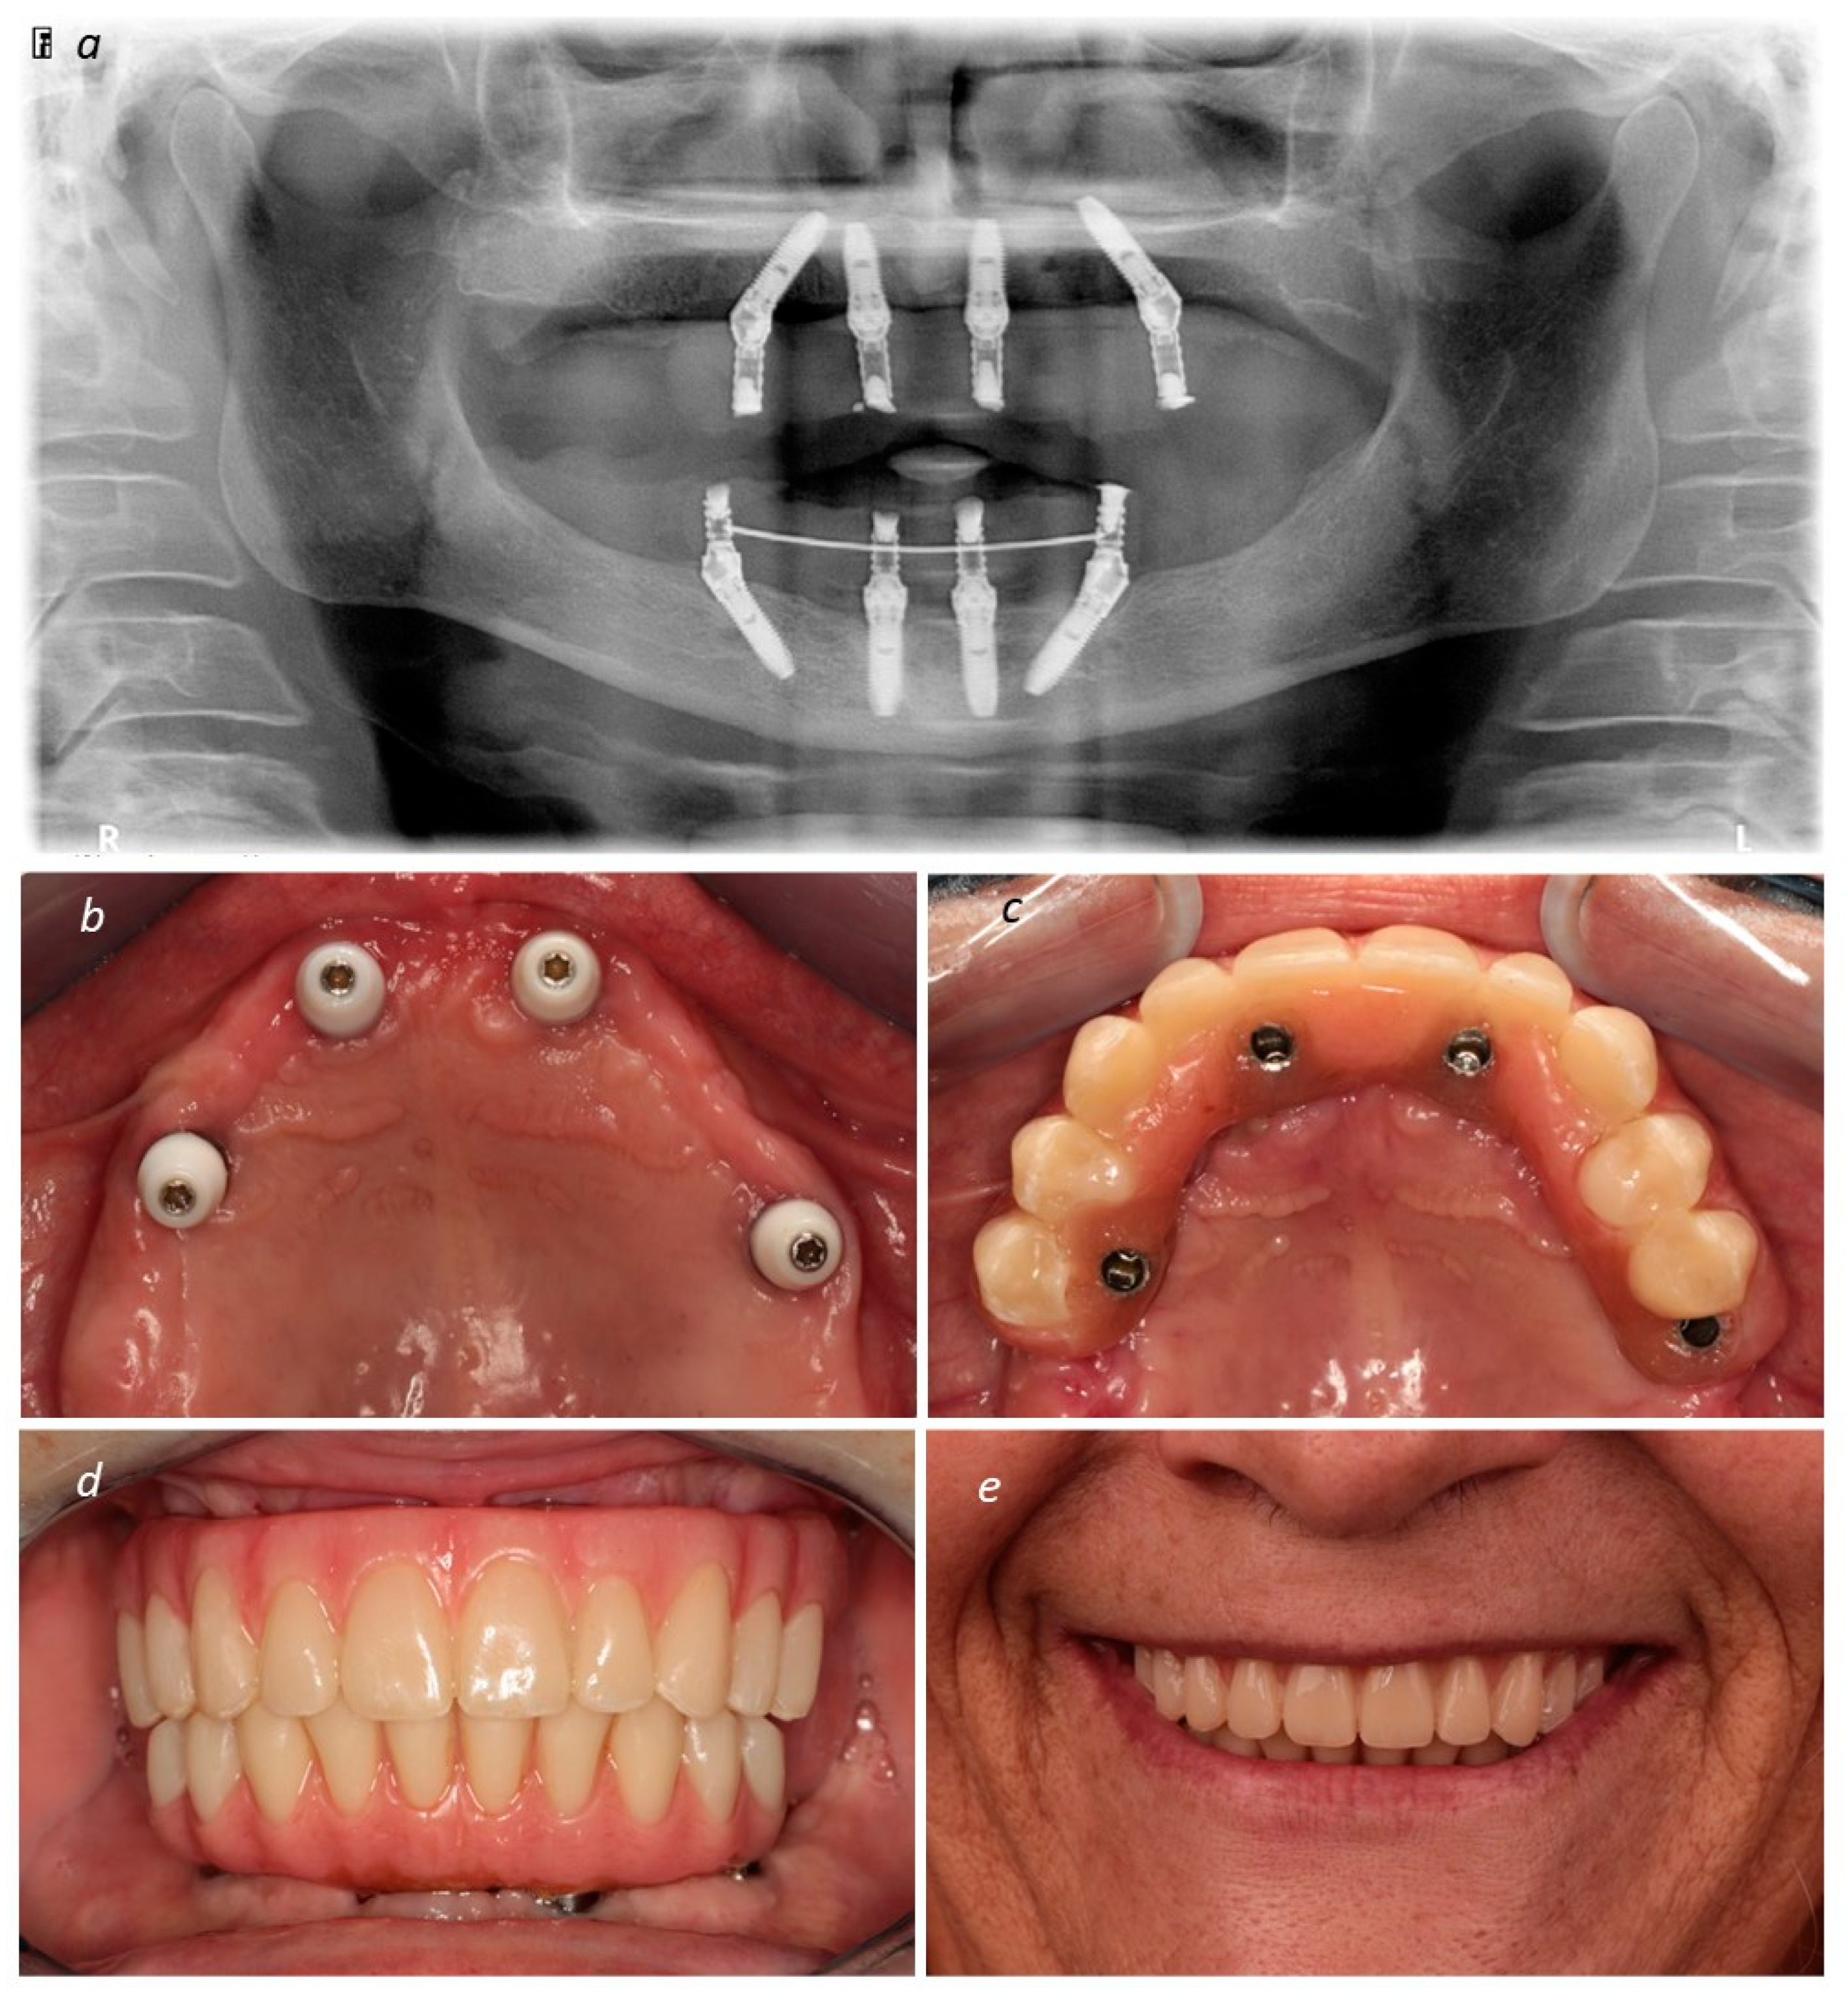

A New Full Digital Workflow for Fixed Prosthetic Rehabilitation of Full-Arch Edentulism Using the All-on-4 Concept

2. Materials and Methods

Description of the Technique

3. Results